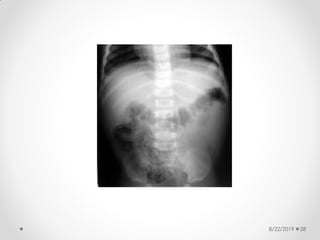

Pneumatosis intestinalis

8/22/2019 28

8/22/2019 29

Abdominal X-ray

findings:

• Dilated bowel loops

• Thickened bowel wall

• Fixed dilated loop

• Scarce or absent intestinal gas

• Pneumatosis intestinalis:

• radiologic sign pathognomonic of NEC

• appears as a characteristic train-track

lucency configuration within the bowel wall